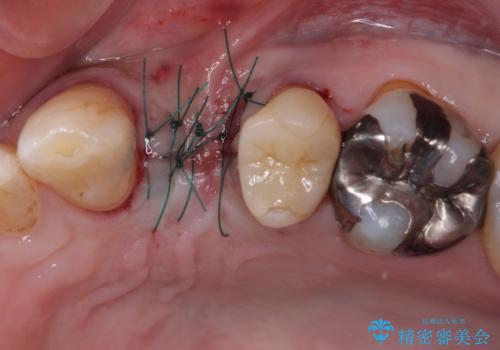

割れてしまった小臼歯 インプラントによる補綴治療

- 他院で抜歯が必要と診断され、再度診断を希望して来院された患者様です。

顕微鏡下で診察を行ったところ、歯根が垂直に破折していたため、抜糸してインプラントによる補綴治療を行うこととしました。

より審美的で、より機能的に優れた治療をご希望とのことであったので、ジルコニアカスタムアバットメントを用いたインプラント治療を行うこととしました。

インプラントは、人工骨を用いた際の骨誘導能が比較的高いとさせるストローマン社のSLActiveを使用しました。